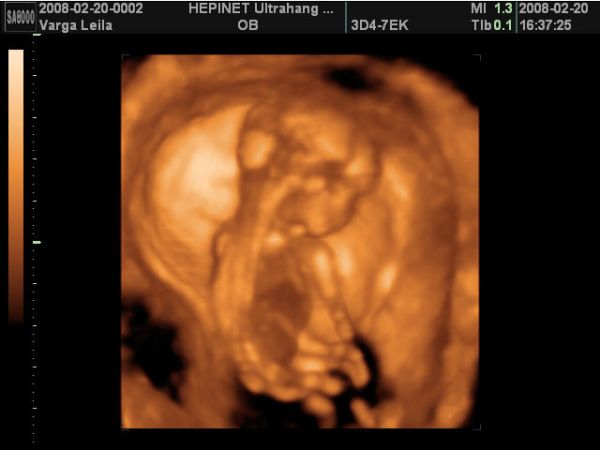

A babó a vizsgálat alatt végig tornázott, izgett-mozgott, úgy nevettem közben, mert annyira jó volt látni, hogy ficánkol, meg homorít a hátával.

A lába között volt a köldökzsinór, és hát eléggé ficánkolt is, úgyhogy csak egyszer láttunk valamit, mikor terpesztett 2D-ben. A nő azt mondta, hogy olyan fiúsnak látszik, de még nem mer biztosat mondani. Szerintem is az lesz, mert én is úgy érzem. De azért a 18. hetin már remélem jól fog látszani.